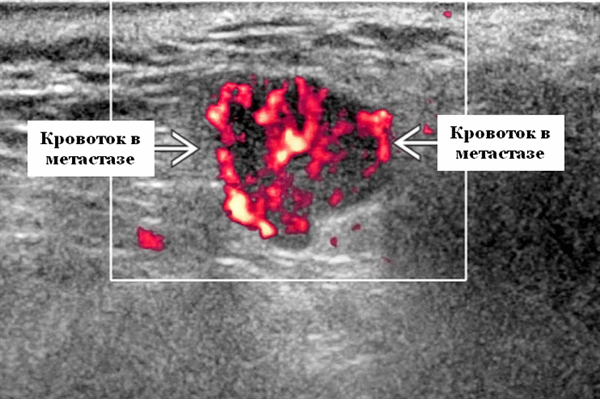

- Интранодулярный кровоток хаотичный / дезорганизованный или преимущественно периферический

Энергетический допплер. Внутриочаговая васкуляризация. Хаотический / дезорганизованный или преимущественно периферический кровоток

- Серошкальное УЗИ. Спектр сонографических находок от простых кист до смешанных и солидных образований. Кистозные, смешанные и солидные поражения могут возникать одновременно в околоушных железах. Кистозные поражения (кисты ДЛК). Хорошо очерченная киста, разного размера, от анэхогенной до гипоэхогенной структуры с задним акустическим усилением. Сеть тонких перегородок ± муральные узлы. Часто встречаются внутренние эхо, которые могут быть мобильными. Сотовидная внешность паренхимы околоушной железы, когда она диффузно изменена з а счет кист. Смешанные поражения (ДЛП). Границы могут быть плохо очерченными, разного размера. Структура преимущественно гипоэхогенная, железы могут быть неоднородными. Без заднего акустического усиления. Солидные поражения (околоушная лимфаденопатия). Множественные овальные / круглые, гипоэхогенные, внутрипаротидные лимфоузлы на УЗИ. Четкий корковый слой ± сохранная корневая архитектура. Сопутствующая реактивная шейная лимфаденопатия

- Цветной допплер. Кистозные поражения: от бессосудистого до умеренного сосудистого кровотока в перегородках, интрамуральных лимфоузлах и на периферии. Смешанные поражения: переменная, васкуляризация от легкой до умеренной. Солидные поражения: внутрипаротидная васкуляризация.